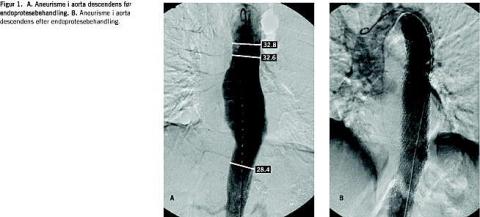

Tabel 1 beskriver patientforløb med indikationer, behandling og de vigtigste tidlige og sene komplikationer. Patient nr. 3 havde et fastsiddende indføringssystem, som blev fjernet kirurgisk. I denne forbindelse var der forbigående underekstremitetsiskæmi. Patient nr. 5 fik overrevet højre arteria femoralis communis, som blev sutureret uden yderligere komplikationer. Patient nr. 10 havde nedsat kraft i venstre underekstremitet kort efter udskrivelsen fra hospitalet. Hos denne patient benyttede man venstre lyske ved endoprotesebehandlingen (Figur 1 ).